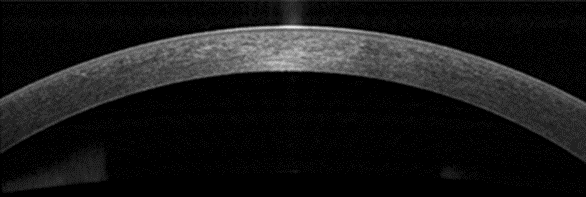

Переход от систем временного домена к спектральным устройствам (так называемым Fourier-domain OCT) обеспечил более высокую скорость сканирования, лучшую проникающую способность и более высокое аксиальное разрешение благодаря использованию более коротких длин волн. Современные системы позволяют получать динамичные, высоко- и сверхвысокоточные изображения с аксиальным разрешением менее 5 мкм (ультравысокое) и более 5 мкм (высокое). Эти изображения дают in vivo представление о структурных деталях конъюнктивы и роговицы (рис. 1) [7]. Недостатком спектральных систем остаётся меньшая глубина сканирования по сравнению с приборами временного домена из-за уменьшенной горизонтальной ширины обзора [3].

Рис. 1. Оптическая когерентная томография переднего сегмента глаза (AS-OCT) нормальной слёзной плёнки и роговицы.

AS-OCT-изображение демонстрирует нормальную структуру слёзной плёнки и роговицы.